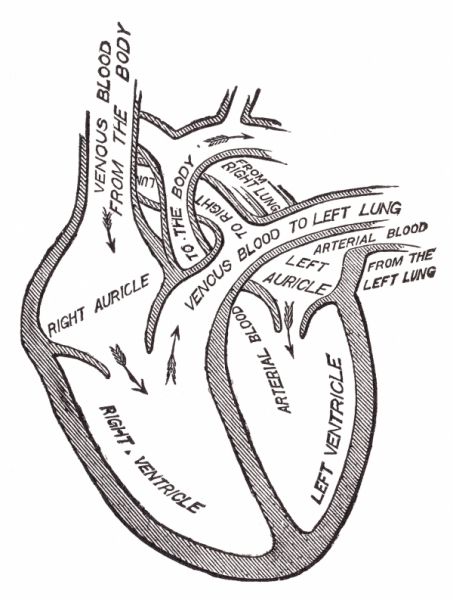

1024x1193 Vintage Anatomical Heart Drawing Vah10 Art

1063x1390 Human Heart Sketch. Anatomical Heart Organ Etching Drawing

722x900 Heart Anatomy, 18th Century Photograph By